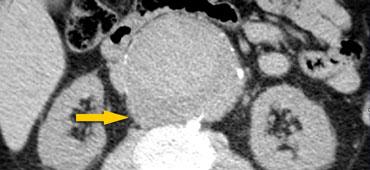

Dấu hiệu động mạch chủ phủ

Bên trái là bệnh nhân nhập viện vì đau lưng.

Hình ảnh ngoài cùng bên trái cho thấy một chỗ phình ra của động mạch chủ.

Đây có thể là biểu hiện của sự yếu khu trú thành động mạch chủ hoặc rò rỉ khu trú.

Thật không may, bệnh nhân này được đọc kết quả là không có rò rỉ và được xuất viện từ khoa cấp cứu.

Hai tuần sau, bệnh nhân bị vỡ phình hoàn toàn.

Rò rỉ có thể xảy ra tại vị trí phình ra (mũi tên).